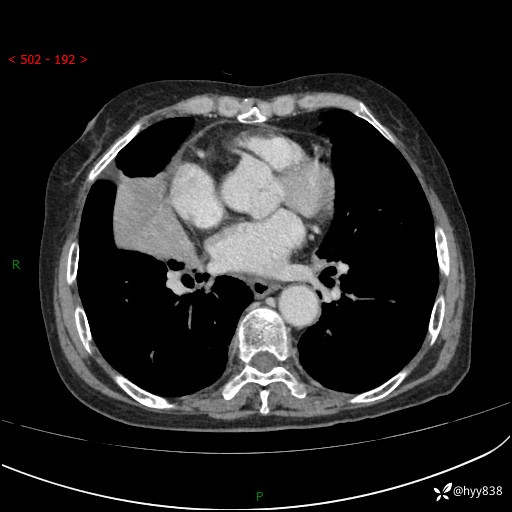

胸部CT增强(外院平扫)